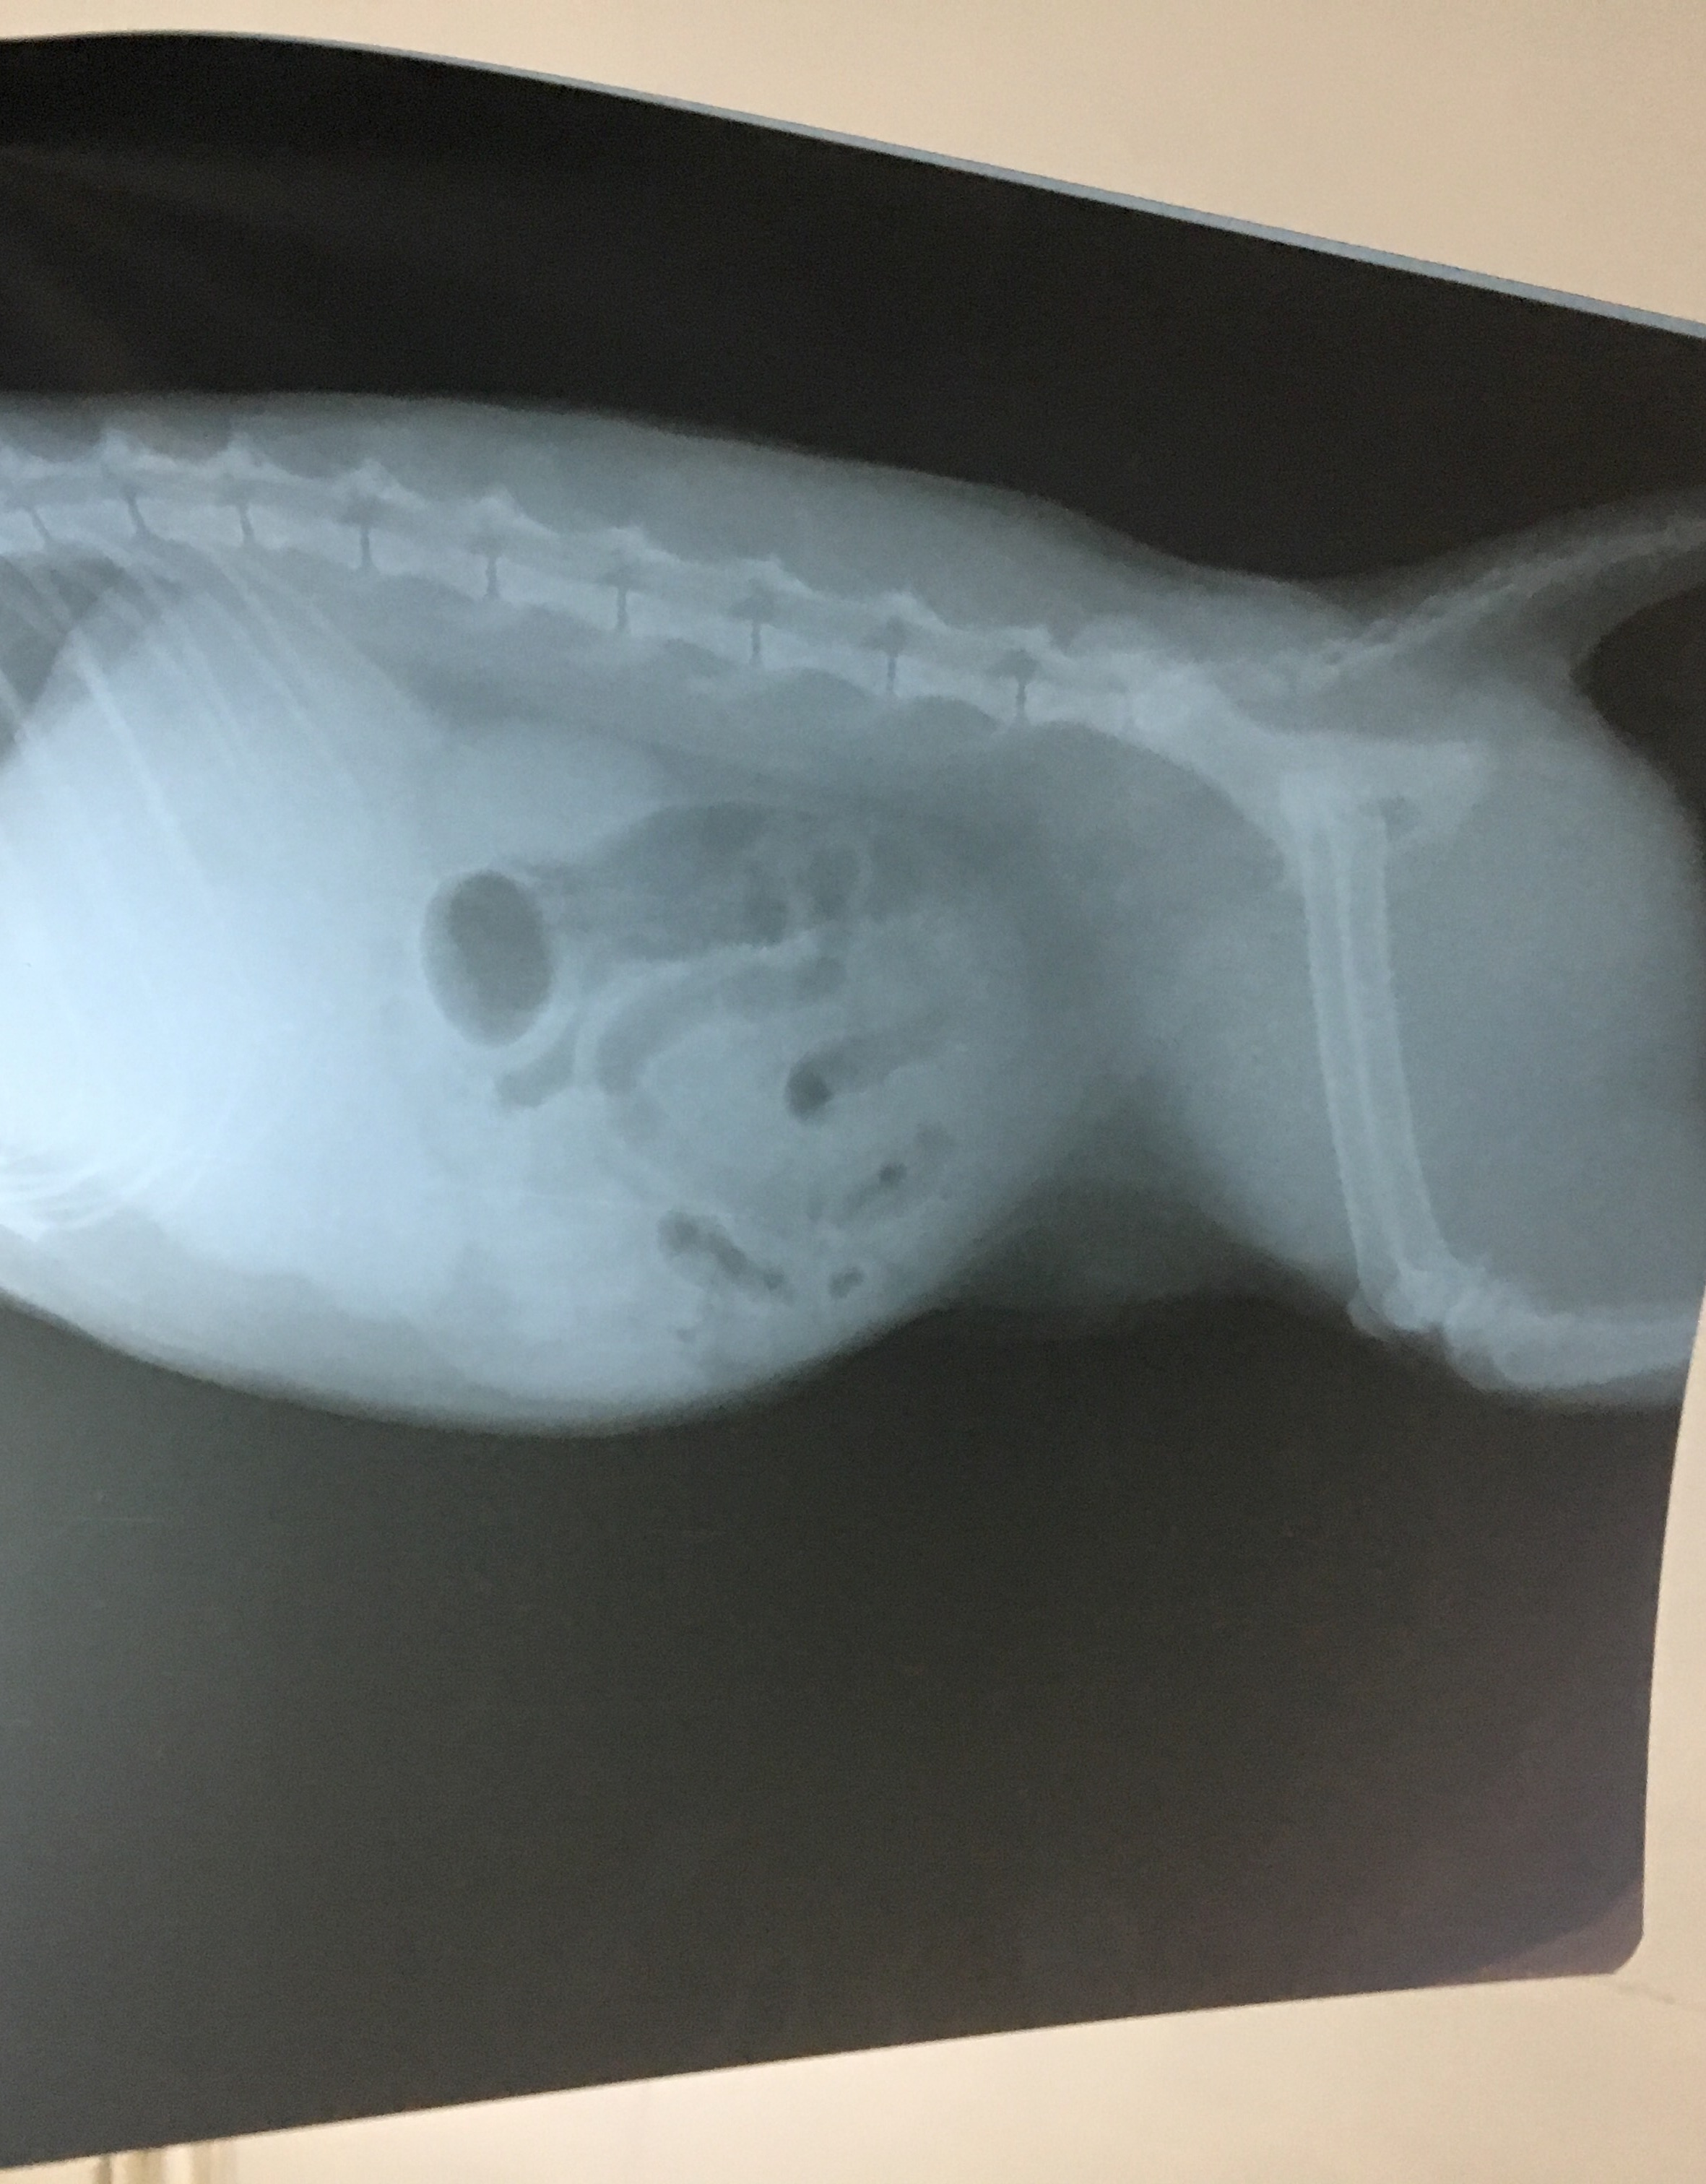

حدود دو هفته اي ميشه كه يه گربه دو ساله رو توسط كسي به سرپرستي قبول كردم. متاسفانه ديگه اون ادم رو پيدا نكردم. مشكل اين گربه ورم شديد شكم هستش در حدي كه من اول فكر كردم حامله ست. روزى ١٥٠ گرم غذاي خشك رويال كنين ميخوره و ٨٠ گرم پوچ دكتر كلايدرز و ٧٥٠ گرم آب. در هر ٢٤ ساعت ٦ بار ادرار و ٣ بار دفع داره كه تقريباً شُل هستش.

عكس راديولوژي شو براتون گذاشتم. شما شكتون به چه بيماري اي هستش؟

عكس راديولوژي شو براتون گذاشتم. شما شكتون به چه بيماري اي هستش؟( این سوال 9 سال قبل مطرح شد و 9 سال قبل به این سوال پاسخ داده شده است. )